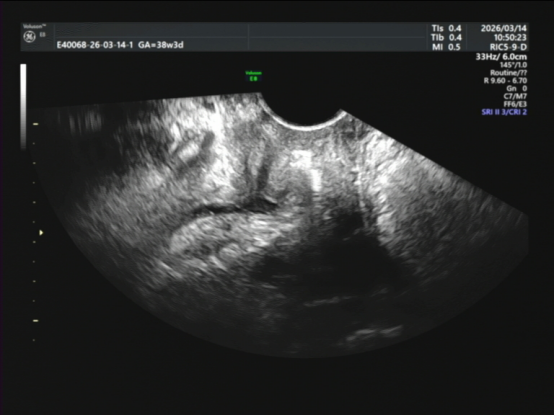

十分钟后,阿姨回来了。我惊讶地发现:石头不见了!

排尿后尿道未见明显强回声